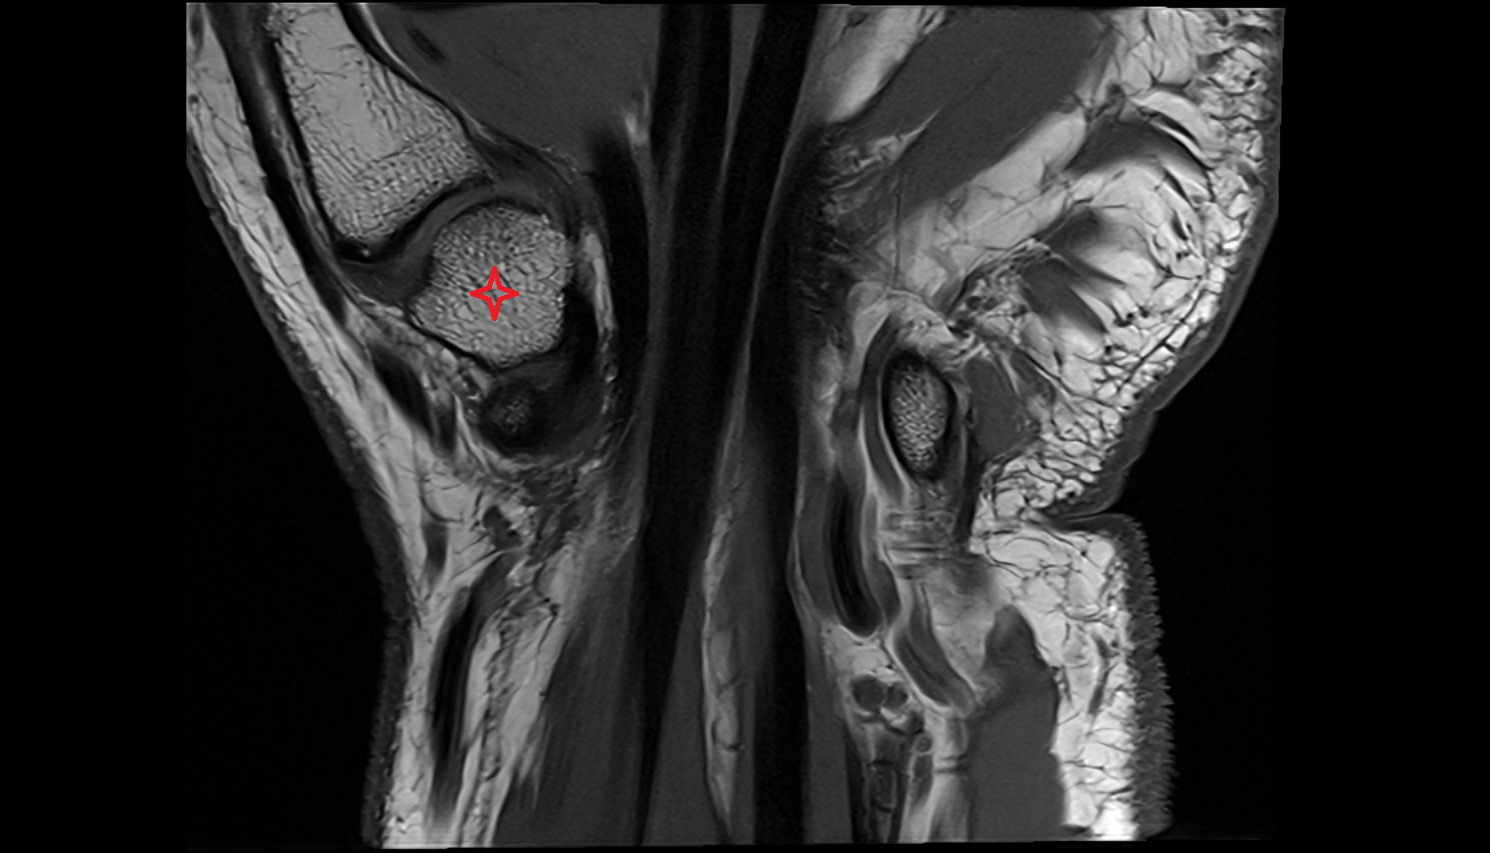

- Knee Joint